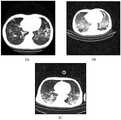

图2:联合治疗组一例重症PCP患者在入院时的胸部CT影像(2A)提示双肺弥漫性渗出明显;在联合治疗7天后复查胸部CT(2B)提示双肺渗出明显减少;Figure 2: The chest CT image (2A) of a severe PCP patient in the combined treatment group at admission showed obvious diffuse exudation in both lungs; re-examination of the chest CT after 7 days of combined treatment (2B) showed that the exudation in both lungs was significantly reduced;

图3:标准复方磺胺甲噁唑组一例重症PCP患者在入院时的胸部CT影像(3A),治疗5天后复查提示双肺渗出明显增加(3B),再经过16天治疗,双肺渗出才出现明显吸收(3C);Figure 3: Chest CT image of a severe PCP patient in the standard compound sulfamethoxazole group at admission (3A). The re-examination after 5 days of treatment showed a significant increase in bilateral lung exudation (3B). After another 16 days of treatment, bilateral lung exudation Only when significant absorption occurs (3C);

图2与图3说明联合治疗方案能更快的改善肺部病变;Figures 2 and 3 illustrate that the combined treatment regimen can improve lung lesions faster;